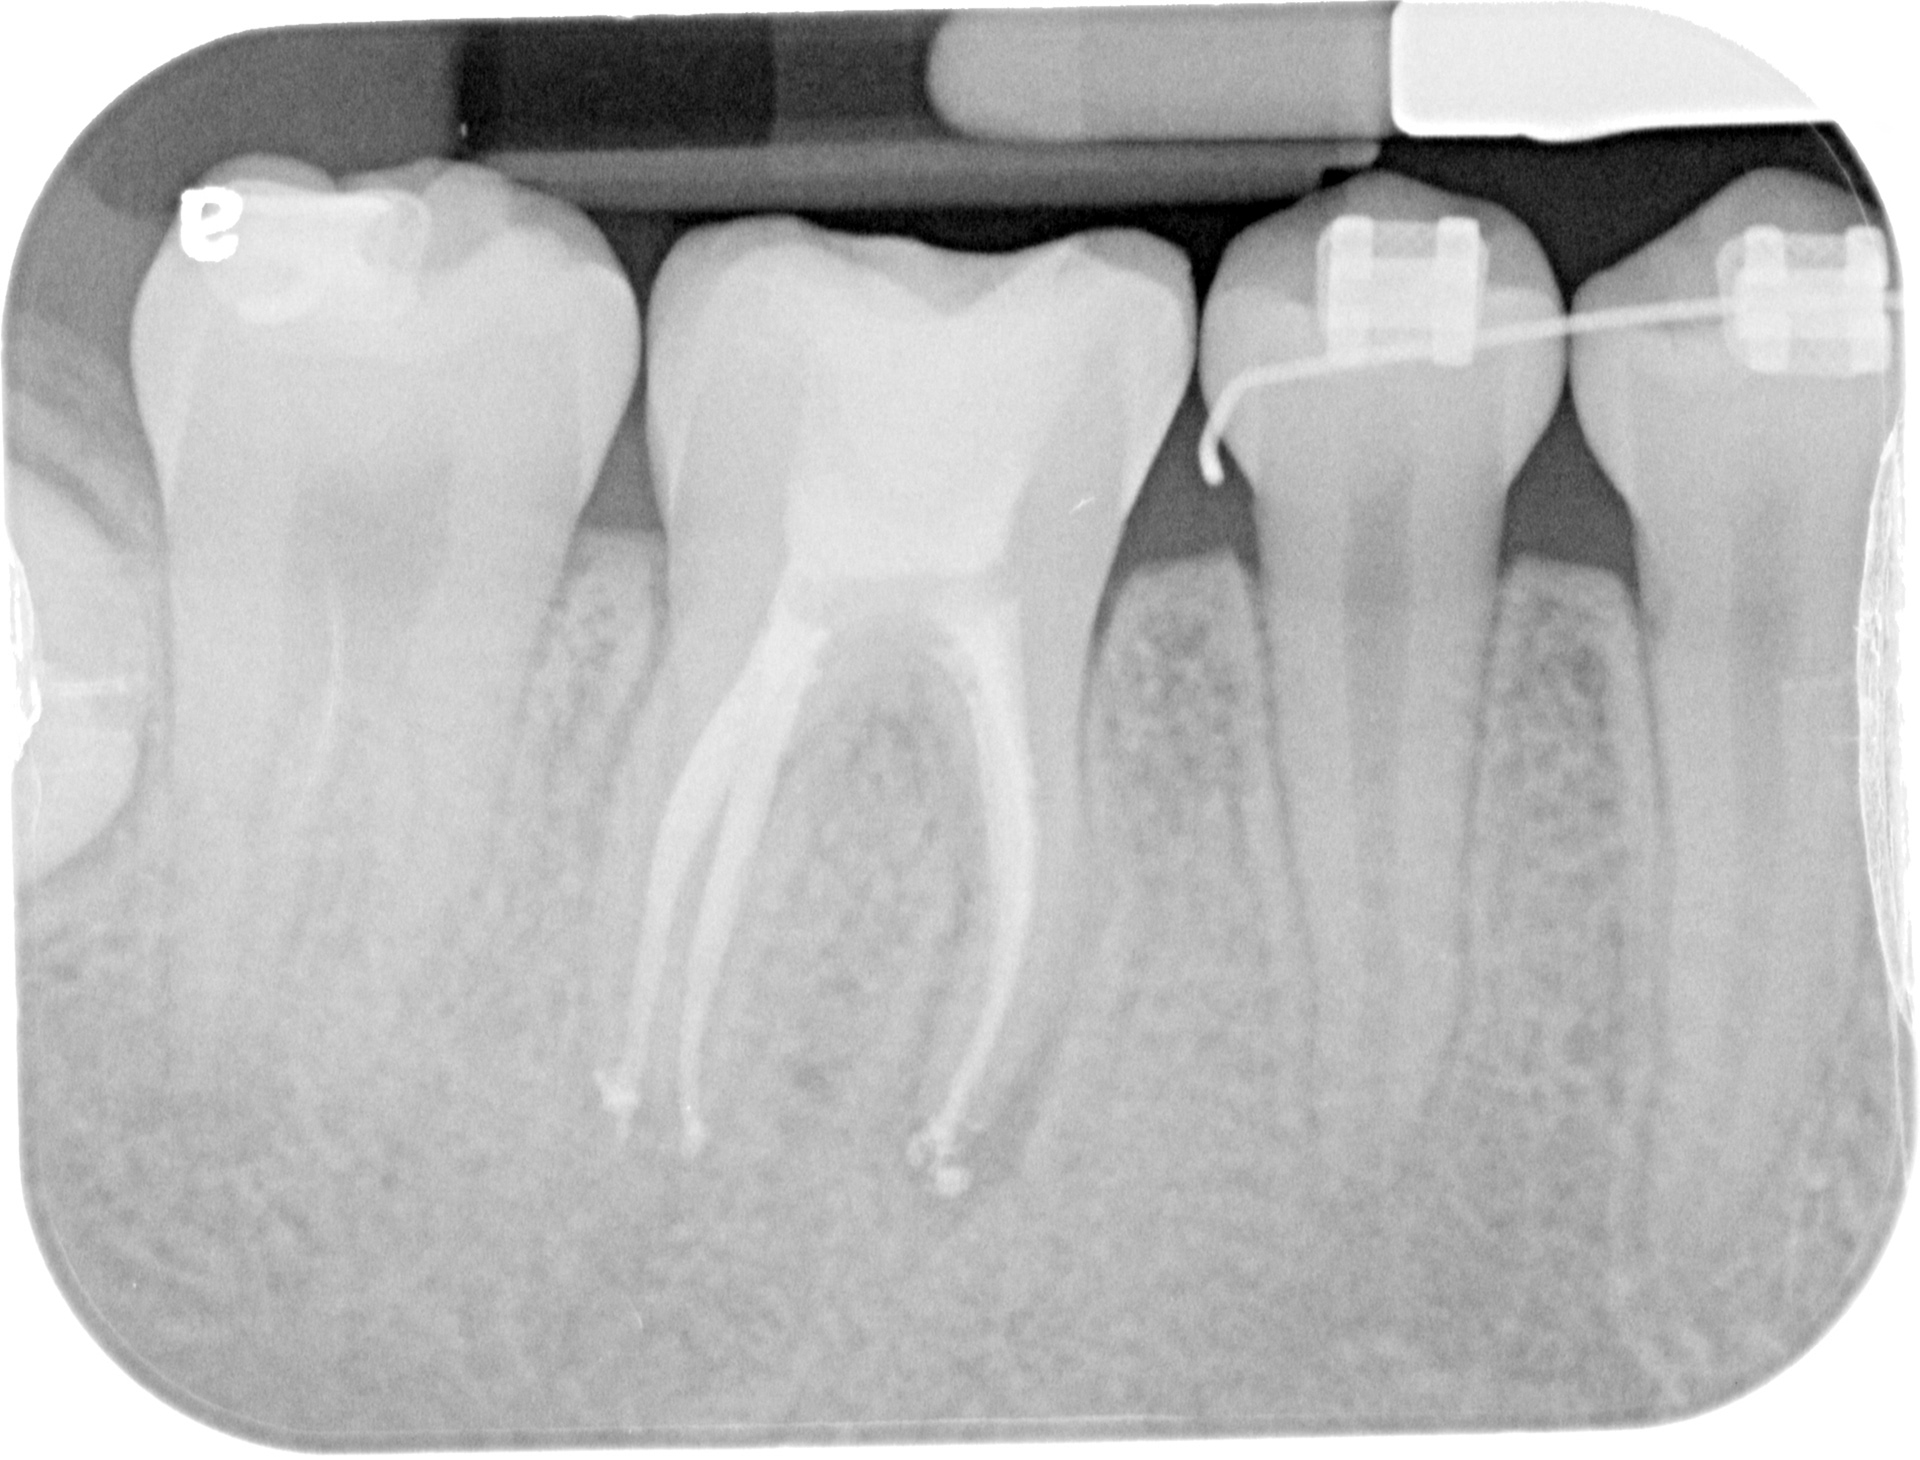

A 46 WITH 4 CANALS

INITIAL

FINAL